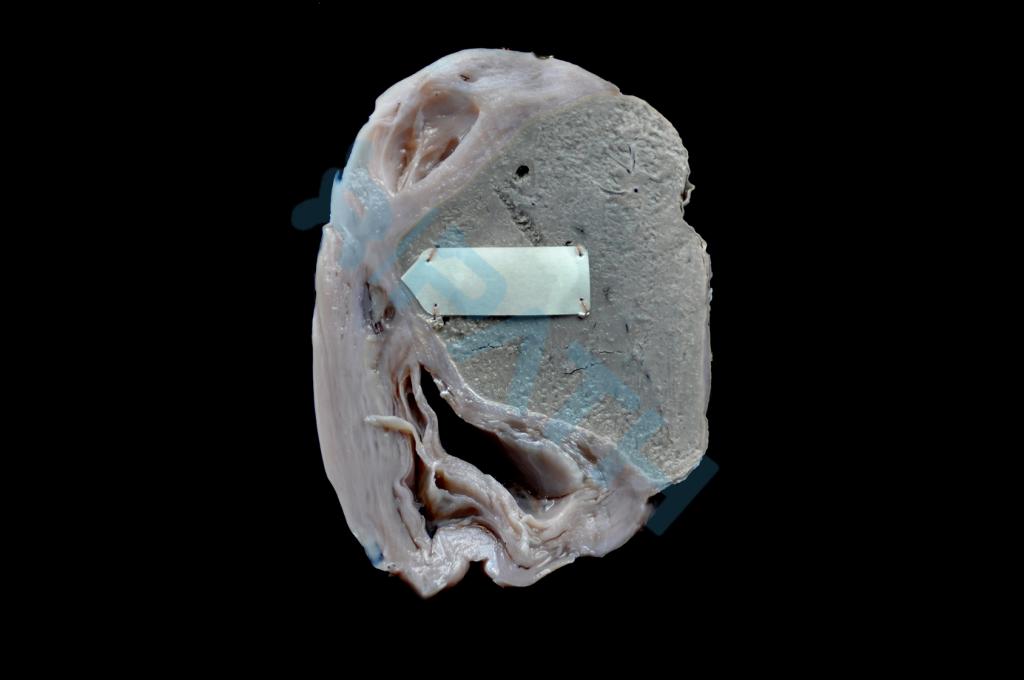

心肌萎缩